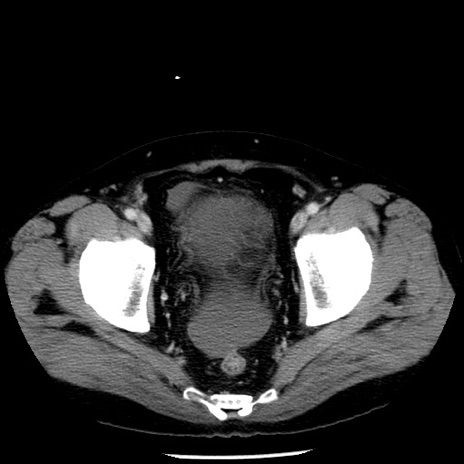

症例29(横断像)

【症例】40歳代男性

【現病歴】2日前から胃痛あり。徐々に周期的な激痛に変化した。本日になっても激痛があるため受診。

【身体所見】意識清明、BT 38-39℃台あり、腹部:膨満、やや硬、右下腹部に圧痛あり。

【データ】WBC 8500、CRP 23.26